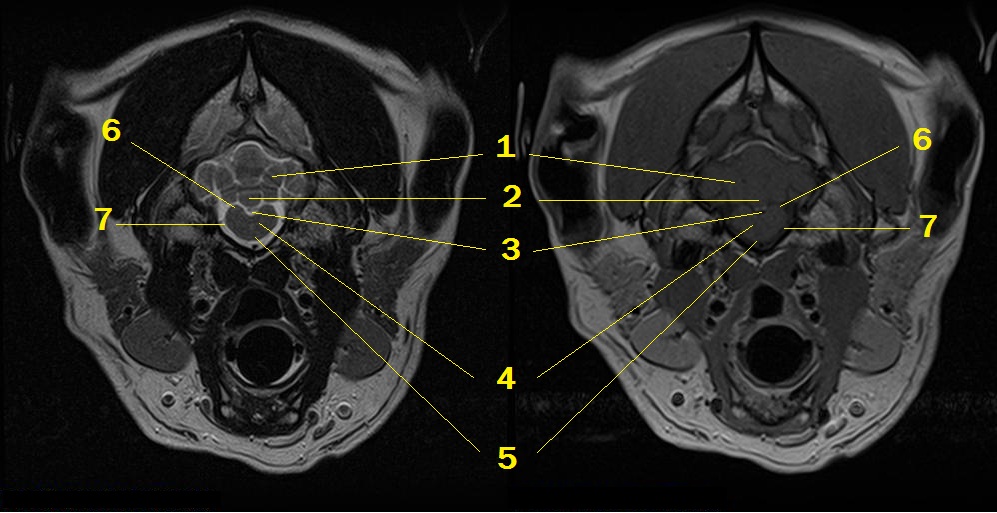

MRI anatomy 13

Q. Identify the structures labeled below:

1. paramedian lobule

2. cerebellar vermis

3. 4th ventricle near the obex

4. medulla

5. pyramid

6. caudal cerebellar peduncle

7. subarachnoid space